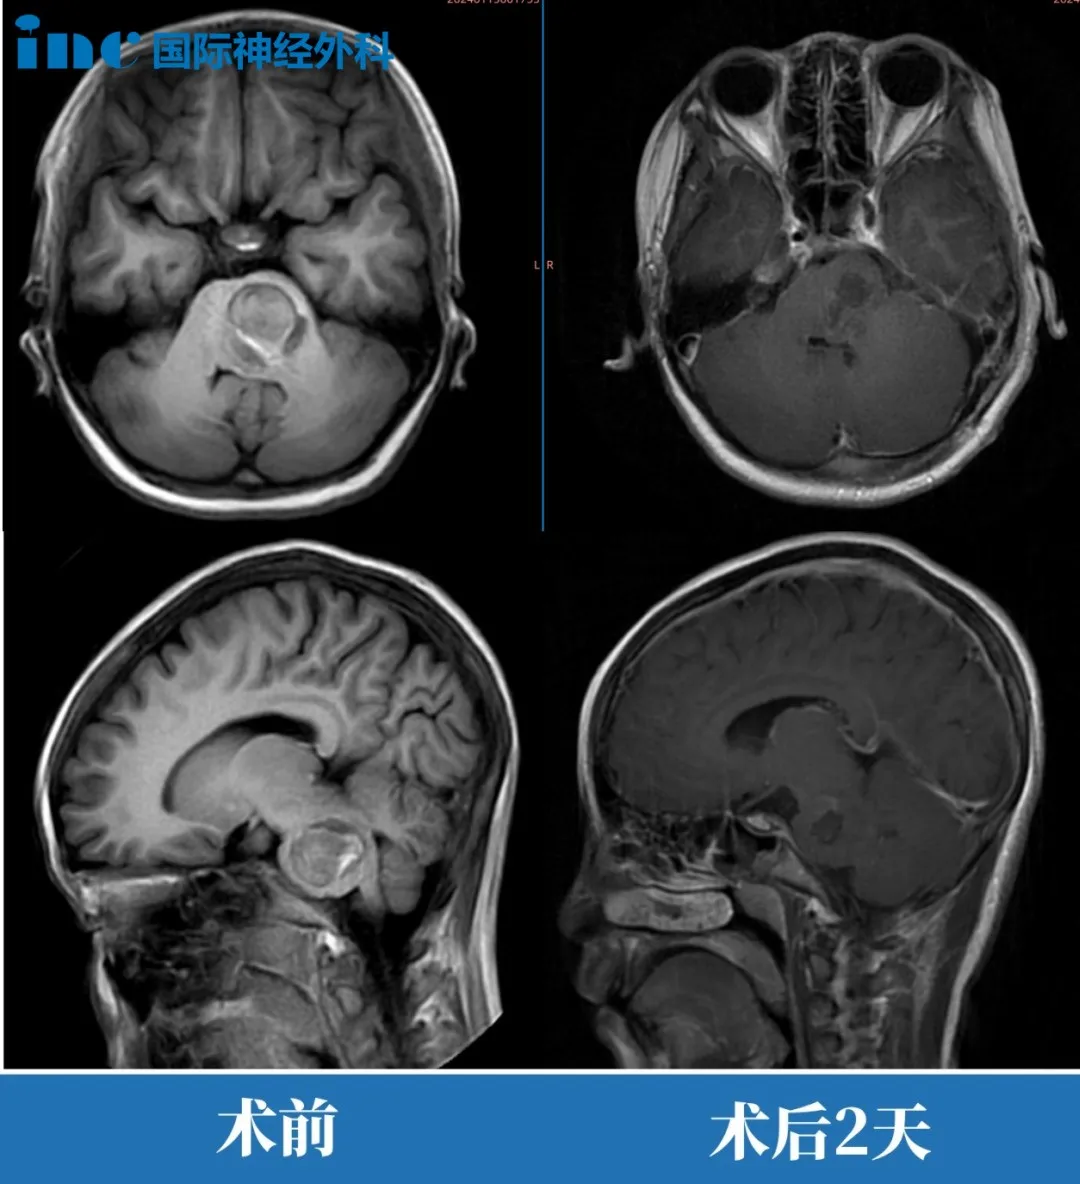

貝貝巴教授示范手術回顧

患者情況:

正在上小學的貝貝,腦干海綿狀血管瘤急性出血、迅速惡化,半身癱瘓,通過120急救送進ICU,如此危機的情況下,還有辦法嗎?

治療回顧:

巴教授1月中國行期間進行了一例示范教學手術,經(jīng)過緊急搶救,不但病灶全切,生命保住,而且意識恢復清醒,四肢活動自如。

影像

▼術后第2天查房,貝貝肢體活動正常。“今天早上吃了好多粥”看著孫女恢復越來越好,貝貝奶奶無比感激,她對貝貝說道“這是救你命的爺爺”。